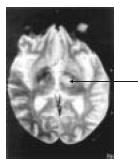

Homem de 38 anos de idade procurou unidade de emergência com déficit motor e sensitivo no membro superior direito, com evolução de alguns dias. Não apresentava náuseas ou vômitos, e sua pressão arterial medida foi de 140x90 mmHg. De antecedente fumava 20 cigarros/dia, mas nega etilismo. Tem antecedentes de uso de maconha, porém nunca usou drogas endovenosas. Ao exame, apresentava hemiparesia direita, sensitivo-motora, de predomínio braquio-facial, com hiperreflexia nos membros à direita. Além disso, foi observado o aparecimento de movimentos coreicos no dimídio direito. Fundoscopia foi normal. RNM com imagens ponderadas em T2 mostram lesão ovalada no núcleo subtalâmico esquerdo, com bordo hiperintenso e centro hipointenso (vide figura). RX tórax foi normal. Hemograma mostrou 2 800 leucócitos, com 300 linfócitos. HIV foi positivo, inclusive no Western blot. LCR lombar mostrou discreta pleocitose, linfomonocitária (14 células) com 52 mg/dL de proteínas e 88 mg/dL de glicose. Testes com látex foram negativos, bacterioscópico e micológico direto, negativos.